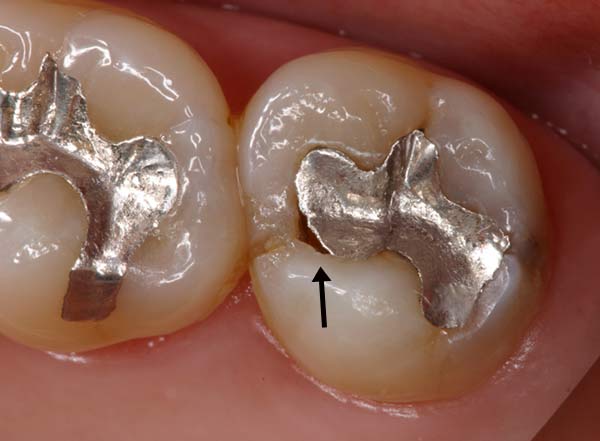

須貝歯科医院では患者さんのお口の中の写真を撮り、説明や経過観察に役立てています。手鏡で口の中を見せられ説明されてもなかなかわからないものですが、写真を見ればすぐわかるものも多くあります。またメインテナンス時に患者さんが来院し不調を訴えられたときに以前の写真があればどこが変化したのかがわかりやすくなります。何年かぶりに来院した患者さんの写真を見比べてあまりの変化にお互いびっくりすることもあります。

歯にものがはさまるという患者さんの写真です。歯の一部が欠けてしまい金属との間に隙間ができているのがはっきりわかります。素人の患者さんが見ても治療が必要であることがわかると思います